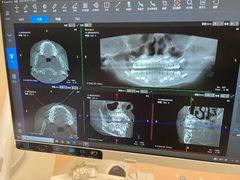

• 德伦口腔(海珠总院)

• -德伦口腔(海珠总院)